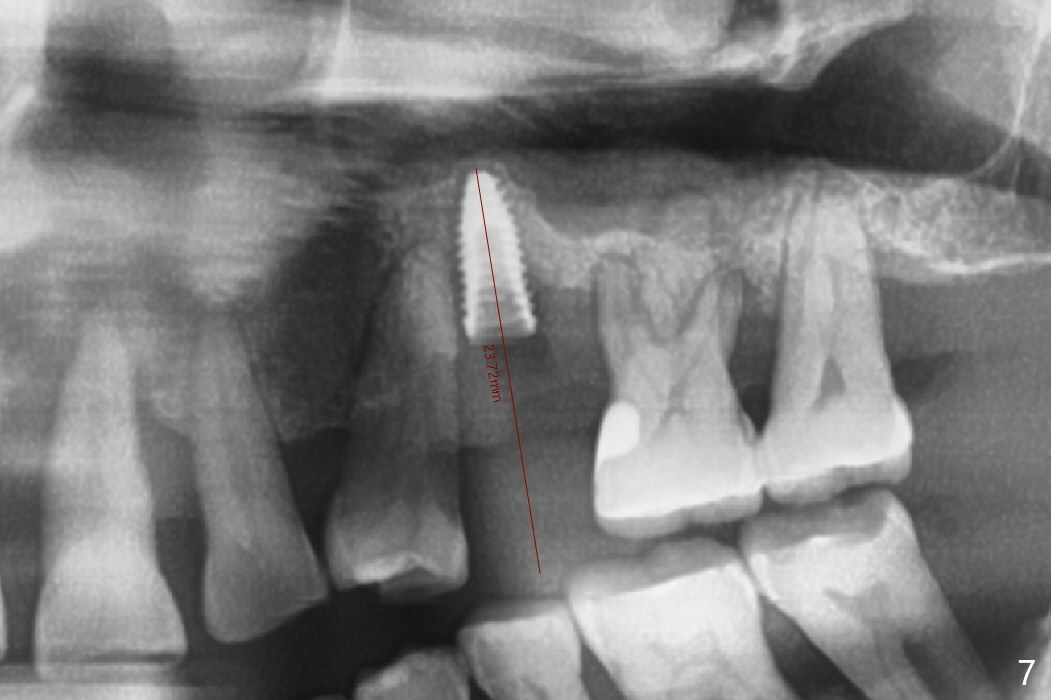

There is more bone apical to the residual root at #13 (Fig.1 red line). An immediate implant along the long axis of the root can be longer, 11.5 mm, favorable for primary stability (Fig.2 (CT taken immediately preop)). The initial trajectory is not ideal (Fig.3). When the pointed/Lindamann bur is removed (Fig.4), effort is made to move the apical end of the osteotomy distal (Fig.5 red arrow) by removing the apical bone (red dashed line). Following sequential osteotomy, a 4x10 mm dummy implant is placed with the trajectory remaining not so ideal (Fig.6,7). As the dummy implant is removed (Fig.8), a new osteotomy is established distal to the existing one (Fig.9). Subsequent drills gradually shift into the original osteotomy (Fig.10 red arrow). When the same dimension dummy implant returns, the trajectory improves with decreased stability (Fig.11). It seems reasonable to place a larger implant without further osteotomy. After placing PRF membrane and Vanilla graft for sinus lift (Fig.13 *), a 4.5x10 mm definitive implant is placed with loss of control in the trajectory (Fig.12,13).